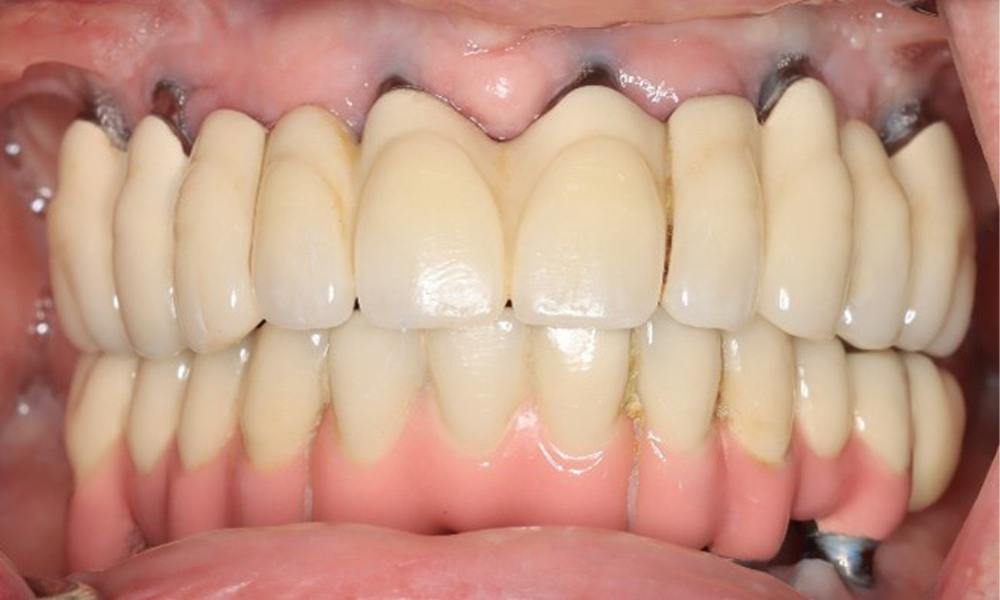

A 74-year-old patient presents for a consultation. The anamnesis shows that the patient has well-controlled hypertension and is taking Lixiana. Additionally, the patient had a kidney carcinoma in 2020. The patient’s lifestyle is unremarkable. She has no natural teeth left and has six implants in both the upper and lower jaws, which are fitted with crowns or bridges. Current findings show no peri-implant mucositis or peri-implantitis; however, there are occasional minor bleeding at the implant sites.

When instrumenting implants, a special approach is required. Choosing appropriate powders and instruments is crucial for preserving the implant surface while ensuring effective cleaning. This includes the targeted use of powder jet devices with specialized perio-tips. The choice of the right powder can be adjusted based on needs and risks, such as considering abrasive levels and dietary requirements (e.g., sugar-free, low-salt).

The peri-implant situation is currently stable. Due to the complexity of the superstructures, the patient has a moderate risk of development and a low risk of progression for peri-implant diseases.